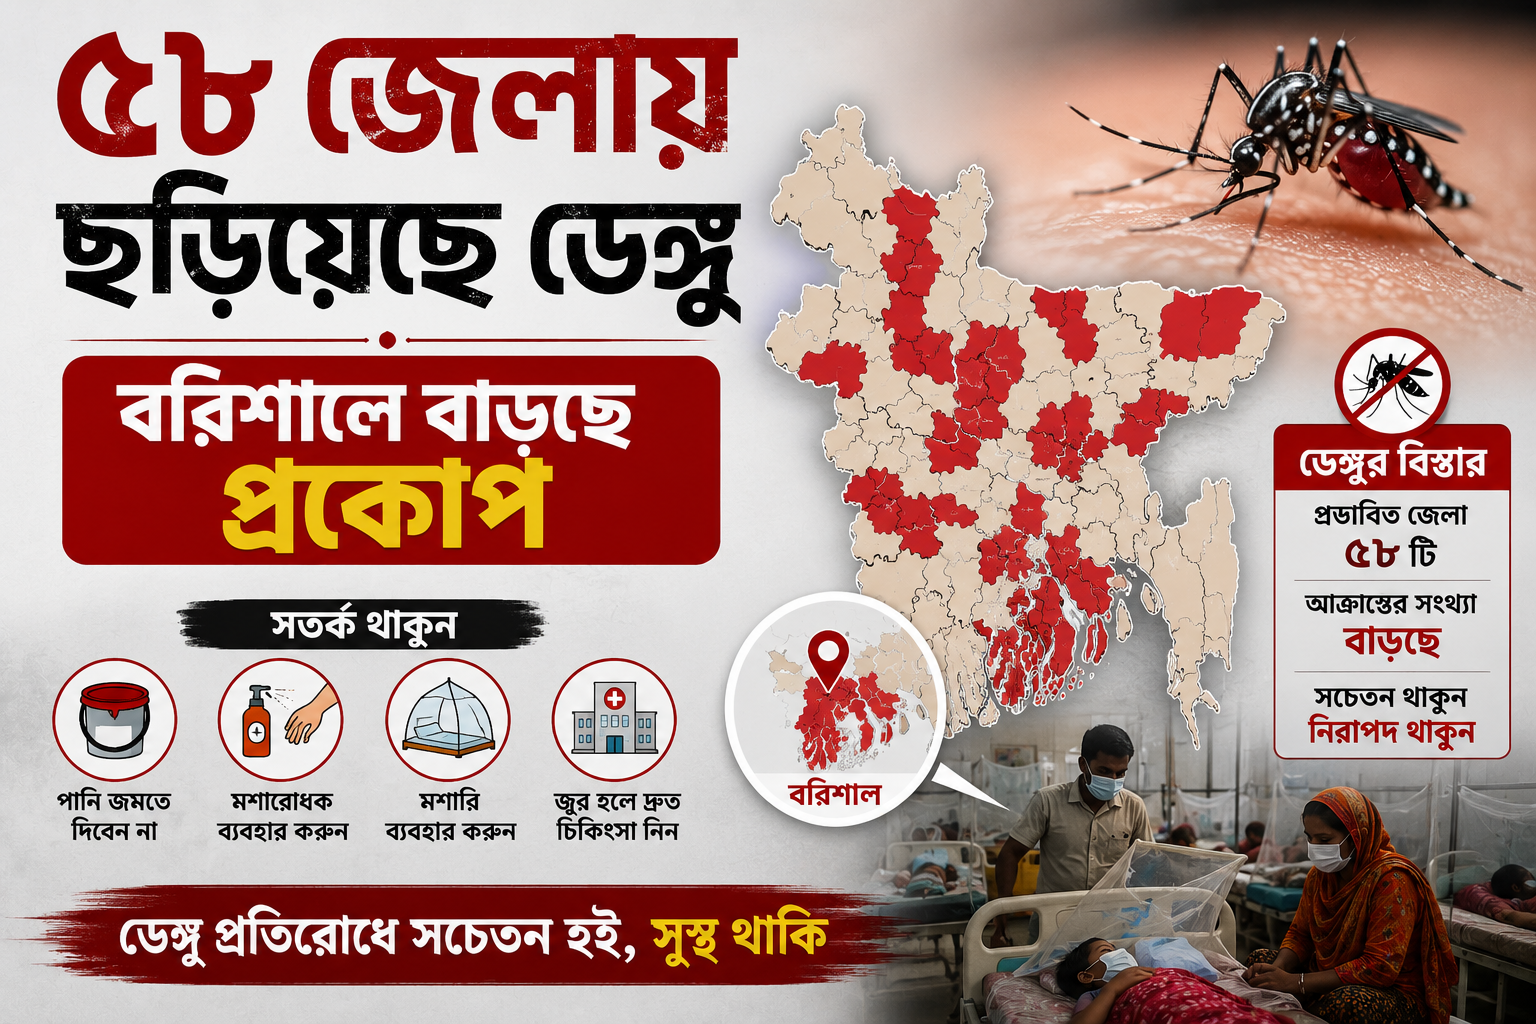

দেশে আবারও বাড়ছে ডেঙ্গুর প্রকোপ। গত ২৪ ঘণ্টায় ডেঙ্গু আক্রান্ত হয়ে পাঁচজনের মৃত্যু হয়েছে। একই সময়ে নতুন করে ১২৪ জন বিস্তারিত..